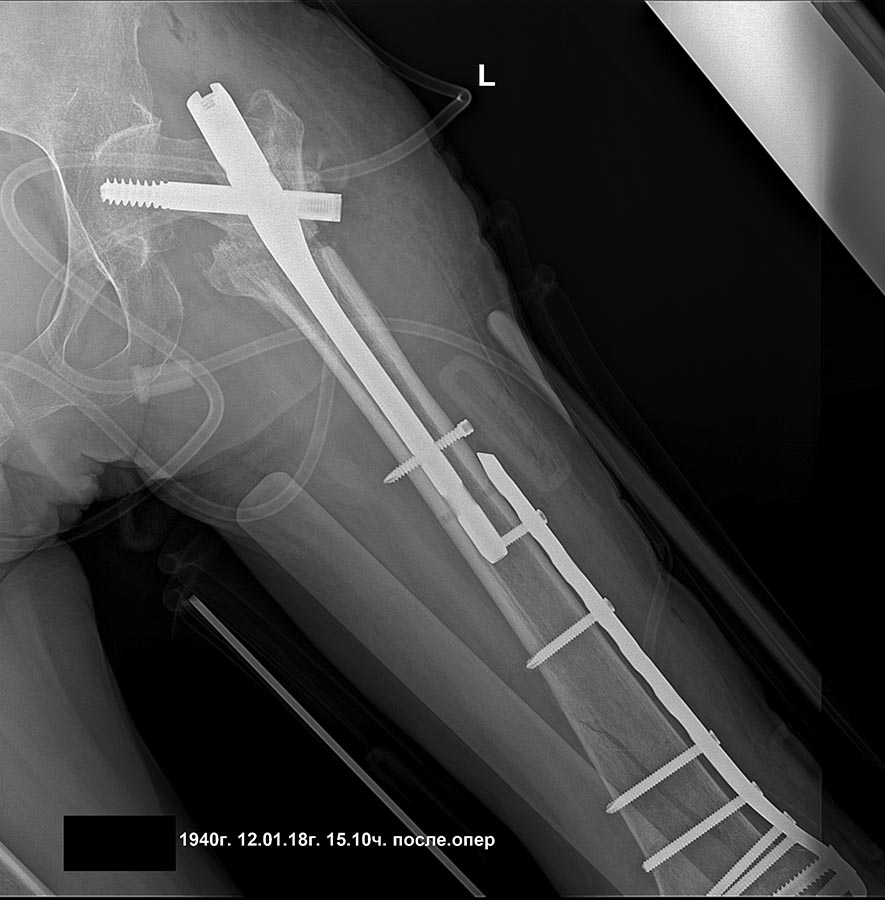

Уважаемые коллеги, прошу высказаться по такому случаю, 4 мес назад чрезвертельный перелом, 2 нед назад при попытке ходьбы с ходункамии нога подкосилась (укороч порядка 4-5 см), и пациентка сломала нижнюю треть. Какие мнения, как сделать поаккуратнее, бабушка 78 лет. Состояние здоровья среднее.

Нижняя треть - - это про диафиз. А тут, похоже, перелом наружного мыщелка бедра. Да, одним гвоздем тут тогда не стоит пытаться. Это две разные проблемы. Дейстительно, для дистального перелома подойдет соответствующая пластина. А в проксимальном отделе - короткий PFN после вальгизации.

добрый день! вроде все получилось сделать,закрыто,чрезкожная остеотомия. дистальная пластина тоже малоинвазивно

бедро